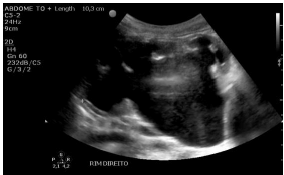

Paciente do sexo masculino realizou exame do aparelho urinário, cujo resultado é mostrado na imagem precedente.

Considerando esse caso clínico, julgue o próximo item.

Em se tratando de uma criança, a primeira hipótese diagnóstica para a imagem corresponde provavelmente ao quadro de megacálices congênitos associado à pelve extrarrenal.

Os diagnósticos diferenciais para essa imagem devem incluir, entre outras possibilidades, estenose da junção ureteropélvica e refluxo vesicoureteral; o calibre do ureter ajuda na diferenciação das duas condições.

A imagem apresentada pode ser identificada tanto em criança quanto em adultos, sintomáticos ou assintomáticos, congênita ou adquirida; no público infantil, pode estar associada ainda a malformações no rim contralateral, como rim multicístico displásico.